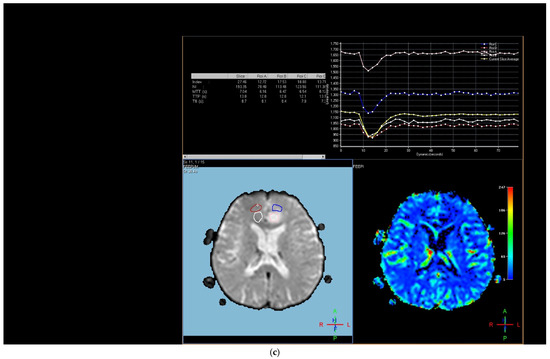

Figure 1. Brain magnetic resonance imaging (MRI) of a 52-year-old male with a low-grade glial tumor revealed (a) increased signal on a T2-weighted image, (b) hypoperfusion with a rCBV of 1.08 in perfusion-weighted imaging, Pink ROI is from tumor and white ROI is from contralateral parenchyma. and (c) a total of four ROIs—one from the peritumoral region (in blue), one from the contrast-enhancing tumoral area (in pink), and two from the contralateral tumor-free white matter areas corresponding to these regions (in white and red) in perfusion-weighted imaging.

The region of interest (ROI) size ranged from 2 to 10 square millimeters in area, depending on the size of the tumor. rCBV values were obtained by identifying regions of maximal perfusion from color maps (Figure 1). While measuring the rCBV values, care was taken to avoid any vascular structures, cerebrospinal fluid, or areas with high susceptibility. For the appropriate placement of the ROI, the rCBV maps were coregistered with FLAIR/T2-weighted, post-contrast T1-weighted, or SWI/GRE images. For multiple metastatic lesions, the measurements were performed from the largest and most enhanced tumoral lesion.

The rCBV values within the tumor and the surrounding area of edema were calculated using the following equation: rCBV = CBV tumoral or peritumoral edema/CBV of the corresponding locations at the uninvolved contralateral brain parenchyma. Perfusion curves were obtained for each lesion. All measurements were performed by the same neuroradiologist (AEP) blinded to the histological diagnosis of the tumors.